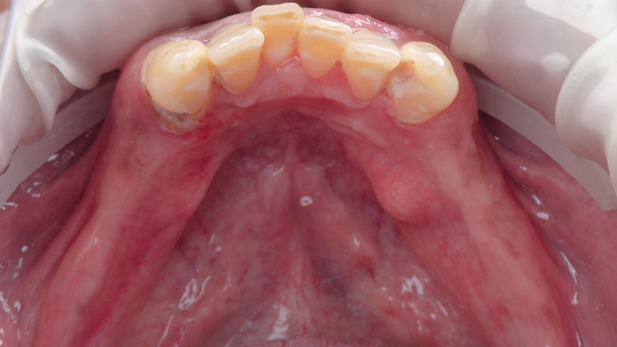

Paciente do gênero masculino, melanoderma, edêntulo superior. Não foram identificadas contraindicações locais ou sistêmicas significativas para a realização do procedimento cirúrgico, e o exame clínico extraoral não apresentava nenhuma alteração significativa. Já o exame clínico intraoral revelou que a região anterior do rebordo superior apresentava-se flácido, e na região inferior foi observada a presença de uma exostose óssea na região de pré-molares esquerdos. Sendo assim, o plano de tratamento englobou a adequação do meio bucal por meio da profilaxia e restauração nos elementos 43, 42, 41, 33 e 32.

A mandíbula do paciente apresentava-se atrófica e tinha ausência dos dentes 34, 35, 36, 37, 44, 45, 46 e 47. Foi então planejada a inserção de quatro implantes e a confecção de pônticos sobre implante. Todo o planejamento foi realizado utilizando o software Exocad, que também foi empregado para a confecção da guia cirúrgica, garantindo a angulação adequada e o cumprimento dos pré-requisitos do implante, além das distâncias de segurança.